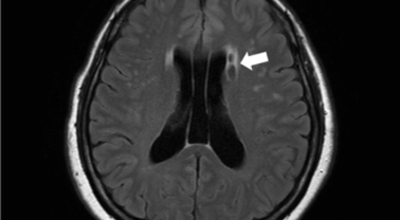

파킨슨병은 도파민 분비 신경 세포의 소실로 발생하는 질환으로 알려져 있는데요 도파민이란 뇌의 신경세포에서 만들어지는 물질로 세포와 세포 간의 신호를 전달하는데 이용되는 신경 전달 물질 중 한가지로 이 도파민이 감소함에 따라 파킨슨병이 걸린다고 하는데 이 도파민 세포가 떨어지는 이유는 아직 정확히 밝혀지지 않았다고 합니다.